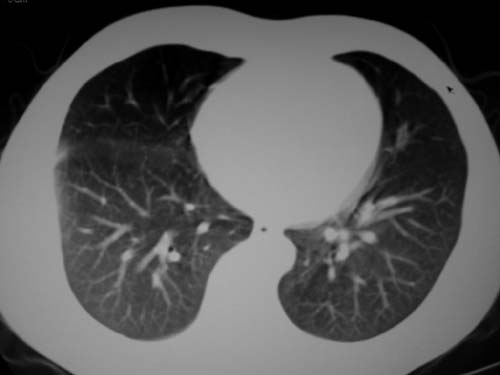

标题: CT19540: 31岁。自述结核性胸水治疗两个月后,在外院拍x线发 [打印本页]

标题: CT19540: 31岁。自述结核性胸水治疗两个月后,在外院拍x线发

病灶也是发生于结核球好发部位,支持结核

考虑结核性结节

结核可能性大。

右侧胸壁结节状软组织影伴相应肺叶内受侵,伴右侧胸腔积液,结合临床,首先考虑结核。